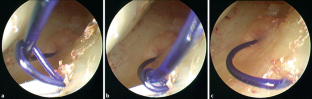

Operationstechnik

Minimal-invasive Naht des Discus triangularis an den Boden des sechsten Strecksehnenfachs unter arthroskopischer Sicht.

Surgical technique

Arthroscopically guided, minimally invasive suture of the TFCC to the base of the sixth extensor compartment.